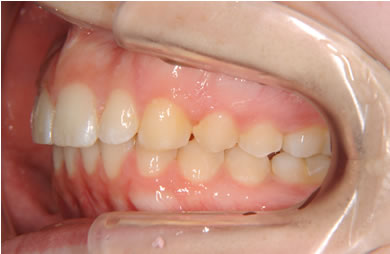

| 性別/年齢 | 女性 / 19歳 | ||||||||||||||||||||||||||||||||

| 主訴 | 上のデコボコの歯を綺麗にしたい。 | ||||||||||||||||||||||||||||||||

| 治療方針 | 上顎の歯の傾斜を正常に治す事で下顎を正常な位置に推進させ、非抜歯にて治療を行う。また、上下の顎のずれの治療のため、装置にゴムを使用し審美的・機能的に良い咬合を獲得させる。 | ||||||||||||||||||||||||||||||||

| 治療内容 | 唇側矯正(シルバー) | ||||||||||||||||||||||||||||||||

| 総治療費 | 659,300円 | ||||||||||||||||||||||||||||||||

| 治療期間 | 1年9ヶ月 |